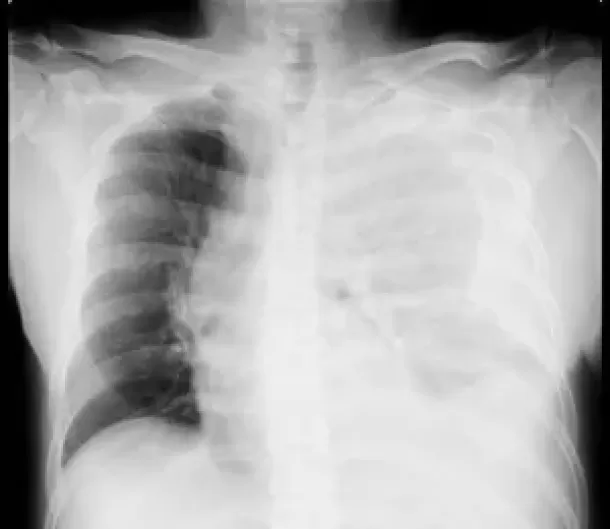

Small-Bore vs. Large-Bore Chest Tubes: Does Size Really Matter for Hemothorax and Pleural Effusions?